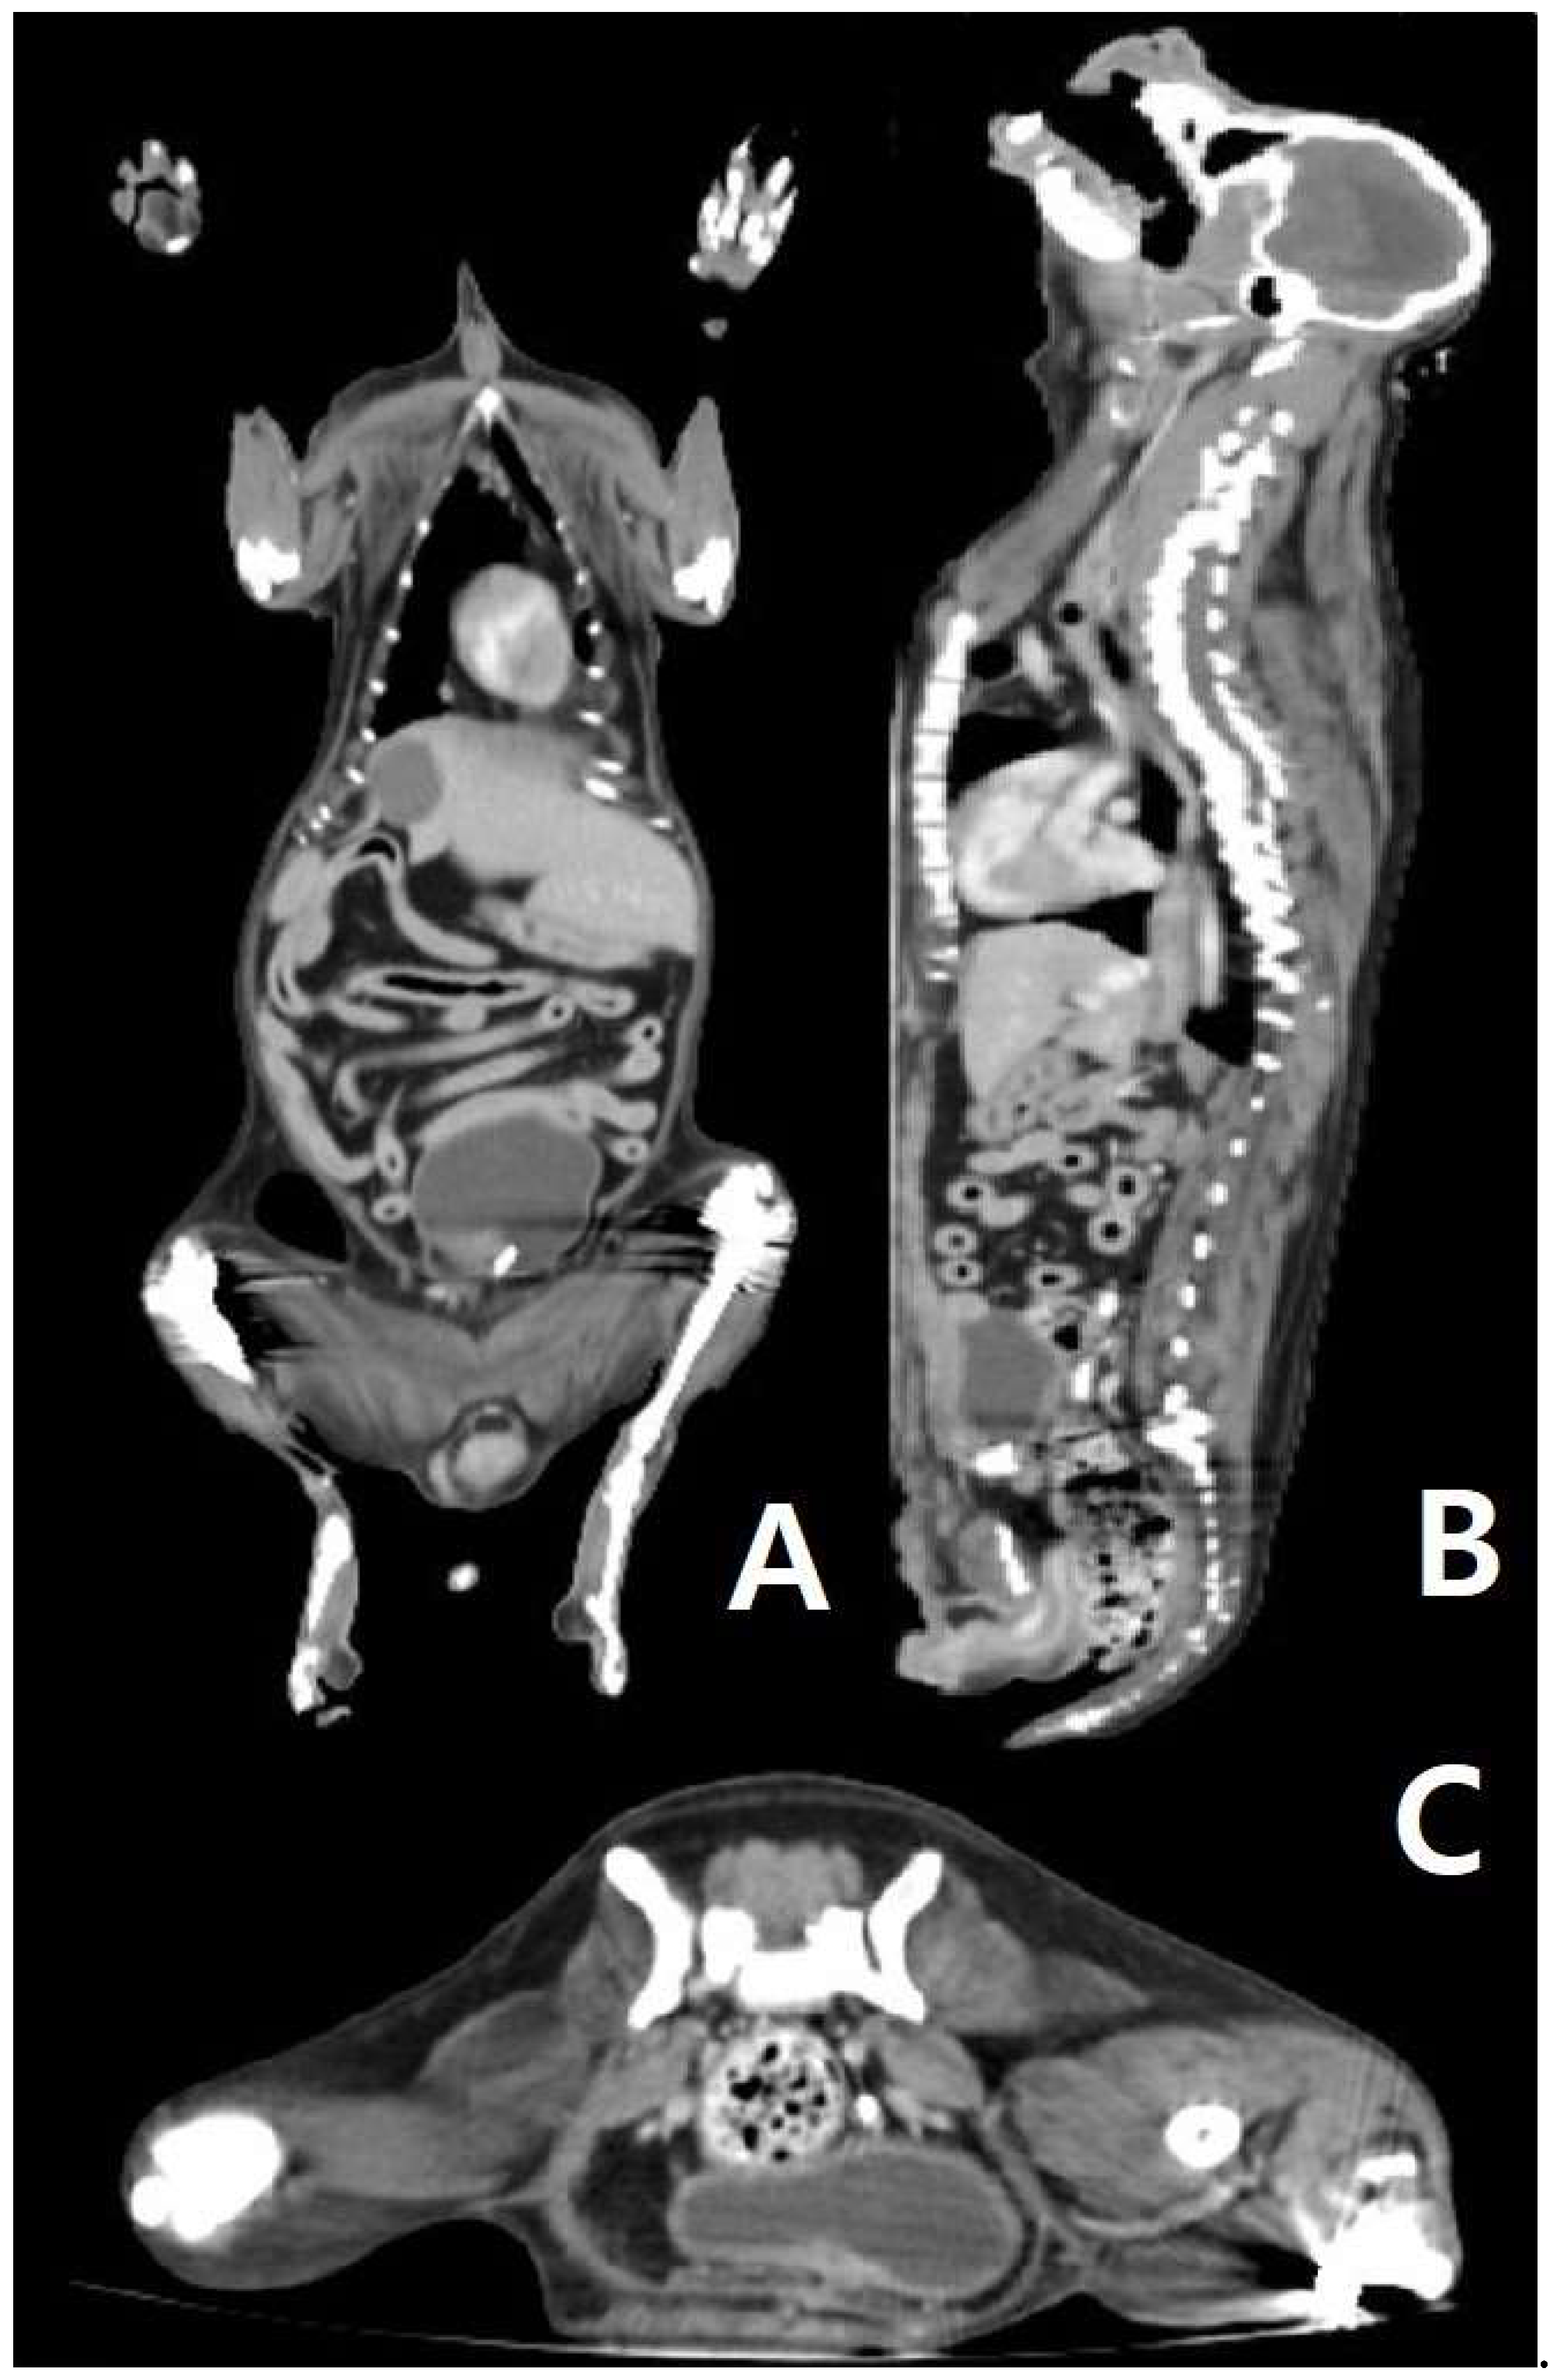

Figure 2. (A, B, and C): CT scan of the patient’s body. (A) In the dorsal view of the CT scan, there is no sign of a primary tumor in the abdominal organ and thorax. (B) In the sagittal view of the CT scan, there is no sign of a primary tumor in the abdominal organ and thorax. (C) In the transverse view of the CT scan (posterior abdomen), there is no sign of a primary tumor in the abdominal organ and thorax.

Based on all imaging tests and biopsies that were performed on this dog, the tumor was diagnosed as a primary mast cell tumor, which originated from the left inguinal lymph node. Even though the findings of histopathological examinations, such as those shown in Figure 1D, are generally seen in metastatic mast cell tumors, they may also be seen in primary mast cell tumors. There were no other findings of primary mast cell tumors in other organs (supplementary figure, figure 2), such as those shown in Table 1, as confirmed through consecutive biopsy and CT scans.

During the process of finding the origin of the MCT, mast cell leukemia, which is rare in dogs 20, was first considered due to the infiltration of the mast cells in the lymph nodes. However, this was excluded since there was no increase in the number of mast cells in a peripheral blood smear. During the first surgery, the large tumor on the left mammary gland and the spleen were removed, and these organs were found to not be a primary MCT. After surgery to identify the primary organ of MCT, even the small nodules found through CT were biopsied, but no suspected mast cell tumors other than the lymph nodes were found. Therefore, the final diagnosis for the patient in this case was a primary MCT of the lymph node and it is significant as being first case to utilize ultrasound, CT scan and biopsy to scrutinize the origin.